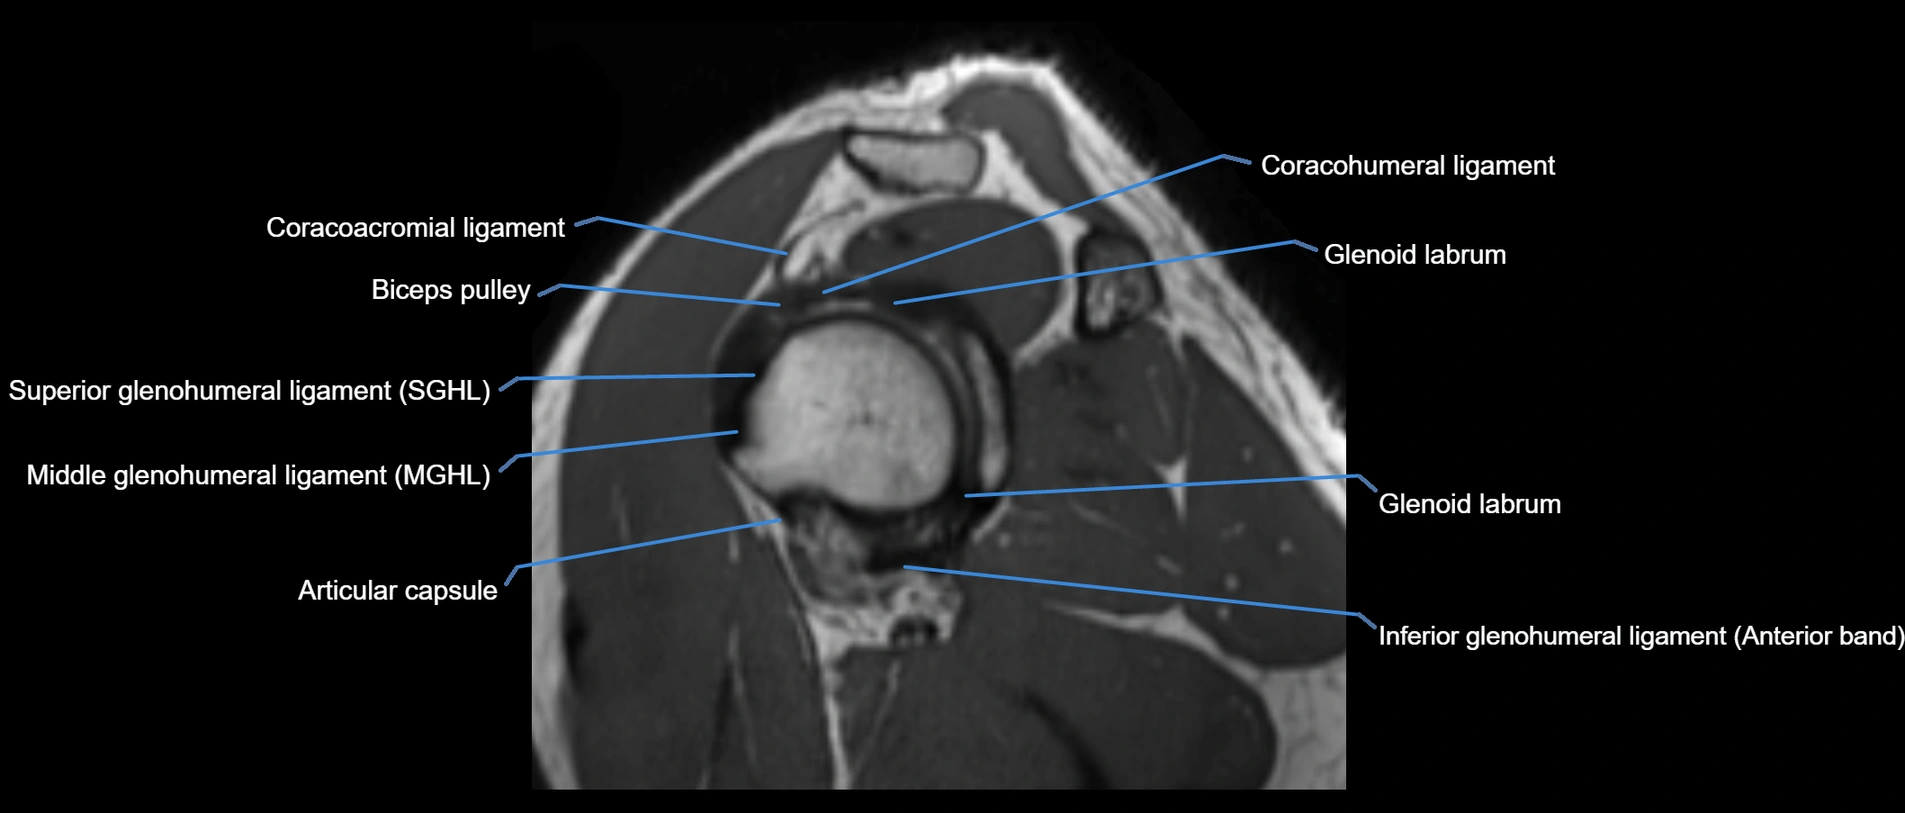

MRI images

image